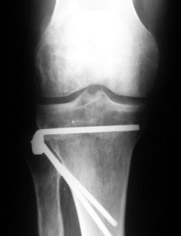

AC> Вот, с учетом и без учета, и на разных уровнях...

Из приведнной схемы не совсеим понял что означают разноцветные линии.

И зачем латерализация периферического фрагмента. Я всегда делаю медиализацию. См схему. И для данного случая медиализация подходит как нельзя лучше.

a> Из приведнной схемы не совсеим понял что означают разноцветные линии.

Черные - это нынешняя механическая ось. Красные - это планируемая правильная ось.

a> И зачем латерализация периферического фрагмента.

;-) Читайте Палея. Стр. 114-115.

a> Я всегда делаю медиализацию. См схему. И для данного случая

Медиализация - это чисто эстетический прием, как я понимаю. Поскольку если делать остеотомию ниже вершины деформации, для восстановления оси надо делать смещение по ширине, в данном случае как раз латерализацию.

А вот на схемке без осей - там на разных уровнях (который правильнее?) устранение варуса чисто открытым клином без медиализации-латерализации. Если как-то так сделать - этого недостаточно будет?